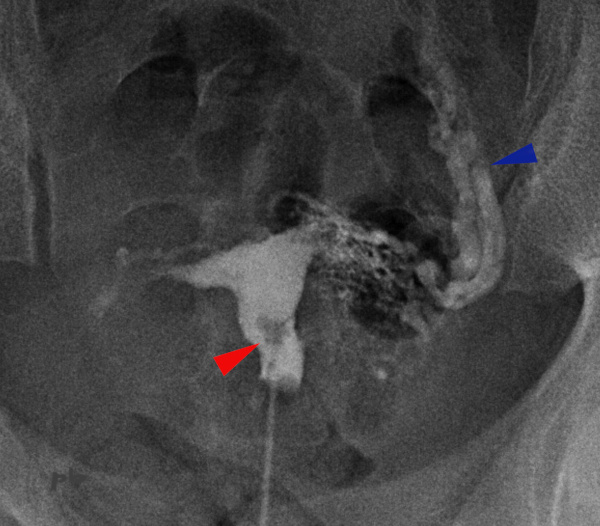

14 – Synéchies – HSG

Antécédents de tuberculose utérine et de chirurgie.

Infertilité.

L’hystérographie montre une image lacunaire (★) persistante sur tous les clichés (un polype s’effacerait partiellement).

Myome calcifié (►)